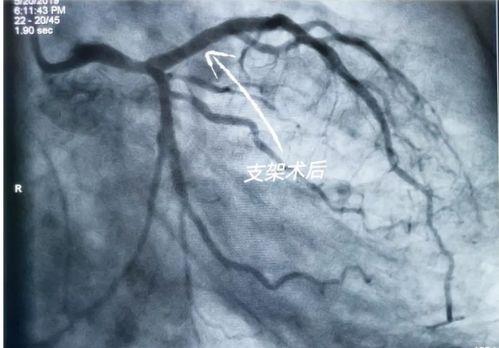

国产心脏支架视频,国产替代之路的里程碑

说起心脏支架,那可是心脏疾病患者的一大福音。心脏支架,顾名思义,就是用来支撑心脏血管的一种医疗器械。在我国,心脏支架的研发和生产一直备受关注。近年来,我国在心脏支架领域取得了显著的成果,成功研发出具有自主知识产权的国产心脏支架。

国产心脏支架在我国的应用非常广泛。据统计,我国每年约有数十万例心脏支架手术,其中大部分采用了国产心脏支架。这些支架在临床应用中表现出良好的效果,为患者带来了福音。